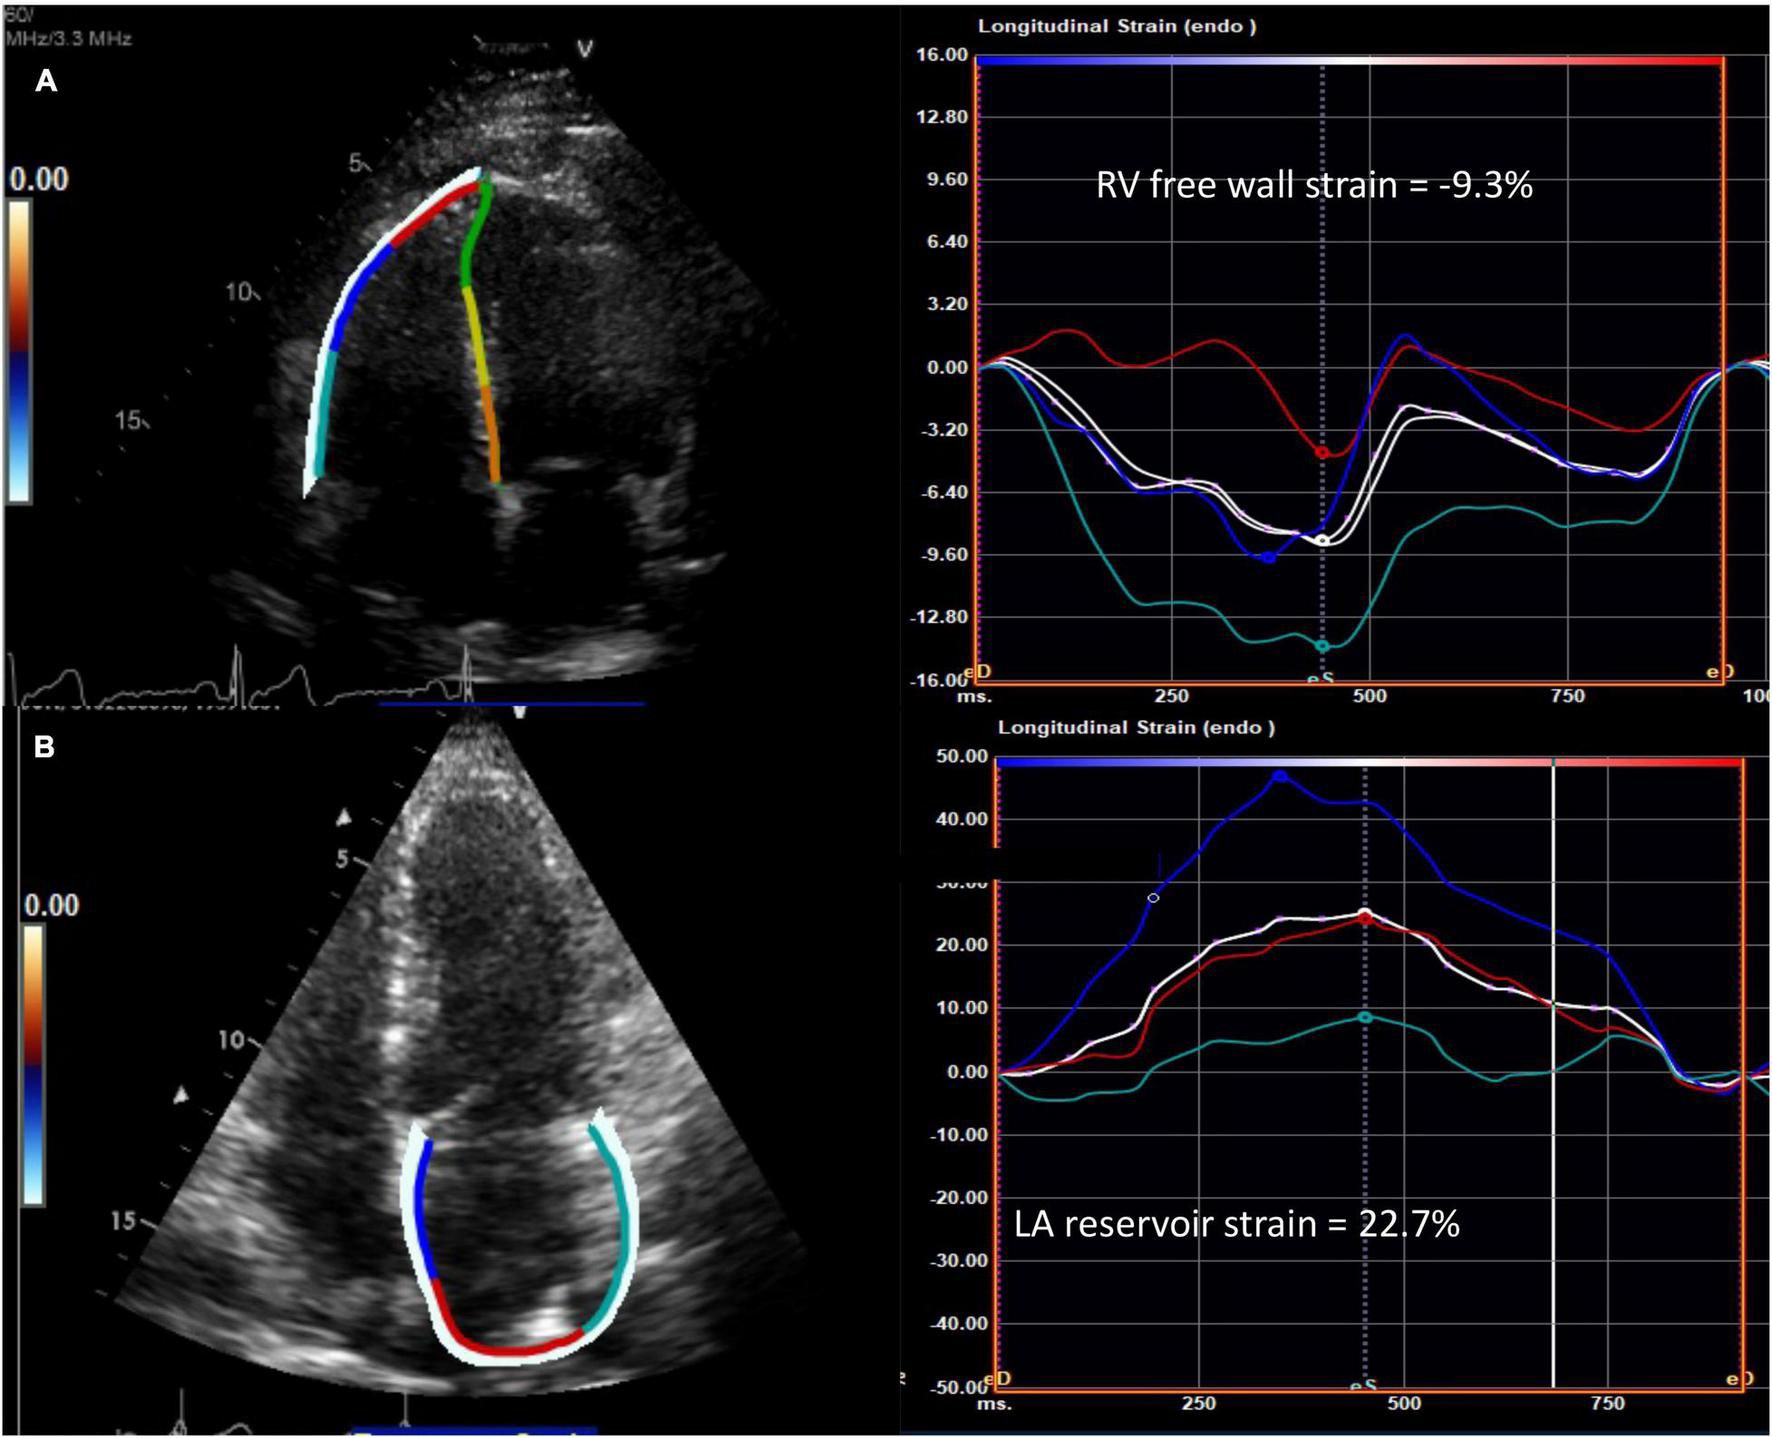

RV longitudinal systolic strain (RVLSS) has been shown to be more abnormal in SSc when compared to controls, despite comparable traditional echocardiographic parameters of RV function between groups (Figure 2) (27). For example, a study by Zairi et al. revealed a 3.3 fold increased risk of subclinical RV systolic impairment in SSc patients, manifested by more abnormal RVLSS, in comparison to controls (-18.2 vs. 22.3%; p = 0.012) (27). Meanwhile, multiple authors have illustrated a regional pattern of abnormal RVLSS seen in SSc patients (10, 28, 29). In a study by Mukherjee et al., 138 SSc patients were compared to 40 healthy non-SSc controls. While both TAPSE and RV FAC were normal in both groups, RVLSS was found to be abnormal in SSc patients, independent of PH and SSc phenotype. Specifically, a regional pattern of abnormal strain was seen in SSc patients, with increased strain in the basal segment and decreased strain in the apical and mid segments. Some hypothesize that the basal segment is hyperkinetic early in the disease course, and as PH develops, the ability of the basal segment to compensate decreases and RV failure ensues, suggesting a “two hit” hypothesis in which pre-existing RV contractile dysfunction may predispose to further dysfunction after PH occurs (28). While STE is a promising technique for detecting unique patterns of early, subclinical RV dysfunction in SSc patients, more evidence is needed to discern its role in this population.

FIGURE 2

Abnormal speckle tracking strain in diffuse cutaneous systemic sclerosis. (A) Example of reduced right ventricular free wall strain (normal <-20%) and (B) reduced left atrial reservoir strain (normal >39%) from the apical four chamber view in patients with systemic sclerosis. The white curve represents the average of the peak systolic strain curves. RV, right ventricle; LA, left atrium.